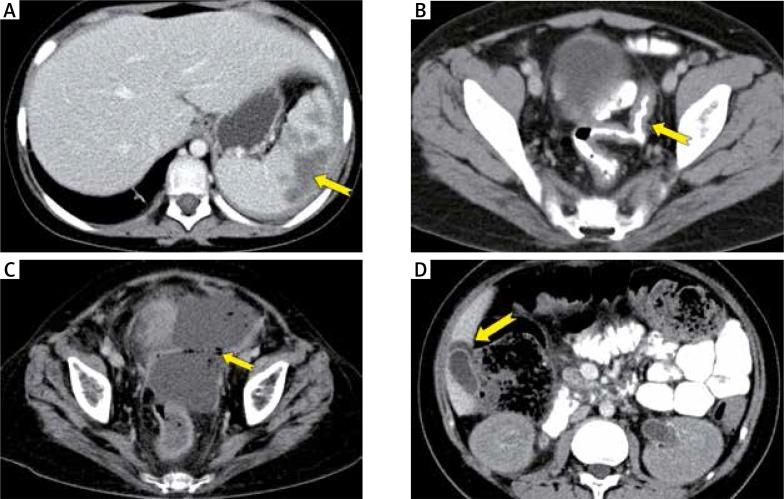

Intestinal CT abnormalities were present in 33 (94%) and extra-intestinal CT findings were in 30 (86%) patients. Thickening of the bowel wall was the most common finding (31 patients, 89%), which involved the small bowel in 29 patients (83%), colon in 16 patients (46%), and both in 15 patients (43%). Oesophageal wall thickening was present in three patients (9%), and gastric wall thickening was in eight patients (23%). Bowel dilatation was detected in 13 patients (37%). Mucosal enhancement of the bowel wall was observed in 28 patients (80%). The prevalence of the extra-intestinal CT findings were: periportal oedema in nine (26%), ascites in 15 (43%), wall thickening and enhancement of gall bladder in 13 (37%), pericholecystic fluid in six (17%), hepatomegaly in 13 (37%), and splenomegaly in nine (26%) patients. One patient (3%) demonstrated free intraperitoneal air due to intestinal perforation.

33例(94%)患者存在肠道CT异常,30例(86%)患者存在肠道外CT表现。肠壁增厚是最常见的表现(31例患者,89%),其中29例(83%)累及小肠,16例(46%)累及结肠,15例(43%)两者均累及。3例患者(9%)出现食管壁增厚,8例患者(23%)出现胃壁增厚。13例患者(37%)检测到肠扩张。28例患者(80%)观察到肠壁黏膜强化。肠道外CT表现的发生率为:门静脉周围水肿9例(26%),腹水15例(43%),胆囊壁增厚及强化13例(37%),胆囊周围积液6例(17%),肝肿大13例(37%),脾肿大9例(26%)。1例患者(3%)因肠穿孔出现腹腔内游离气体。